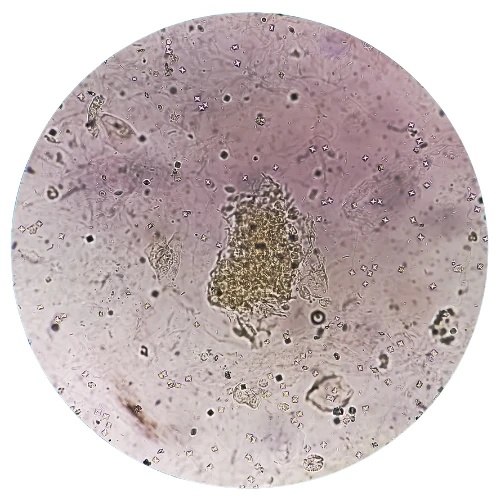

La baciloscopia para BAAR (bacilos ácido-alcohol resistentes) en sedimento de orina es una técnica de laboratorio utilizada para detectar la presencia de Mycobacterium tuberculosis en muestras de orina. Esta técnica es principalmente utilizada en el diagnóstico de la tuberculosis urogenital, que es una forma menos común de tuberculosis que afecta los riñones, la vejiga urinaria y las estructuras genitales. Durante el procedimiento, se recoge una muestra de orina y se procesa para concentrar el sedimento, que contiene células y posibles microorganismos. Luego, se aplica una tinción específica, como la tinción de Ziehl-Neelsen o la tinción de auramina-rodamina, que permite visualizar los bacilos ácido-alcohol resistentes bajo el microscopio.